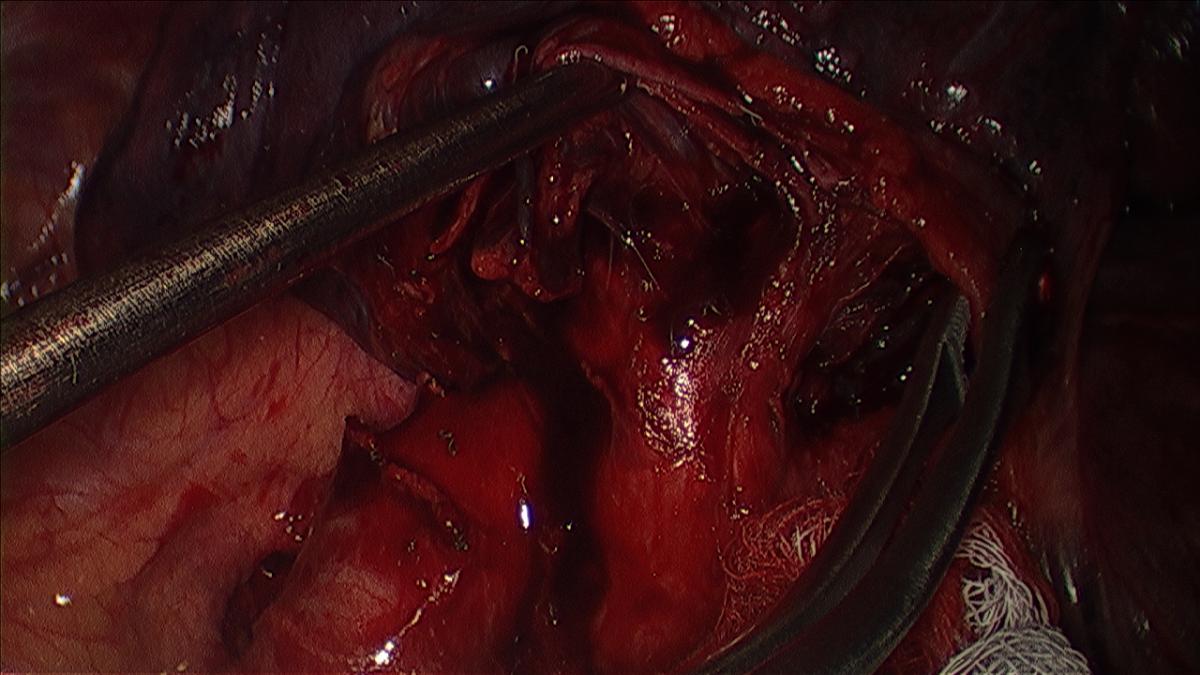

The first pulmonary arterial branch to the left upper lobe, which is the artery to the apico-posterior segment, is dissected sharply and bluntly if adequate exposure is possible. The exposure of the artery is facilitated by retracting the superior vein inferiorly with the sucker (Figure 4, 5).

Any lymph nodes encountered are dissected, removed, and analyzed as described. If exposure is not adequate, the apical tri-segmental vein can be divided as described subsequently. Circumferential isolation of the artery is performed with a thoracoscopic right angle, or curved vascular clamp via the working incision (Videos 3, 4).